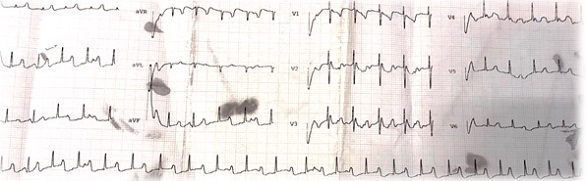

En la actualidad el paciente tiene cinco meses, está asintomático, y presenta frecuencias entre 55 y 70 lpm (Fig. 3). Cardiología realiza revisiones periódicas.

Figura 3. Electrocardiograma actual: BAV de tercer grado